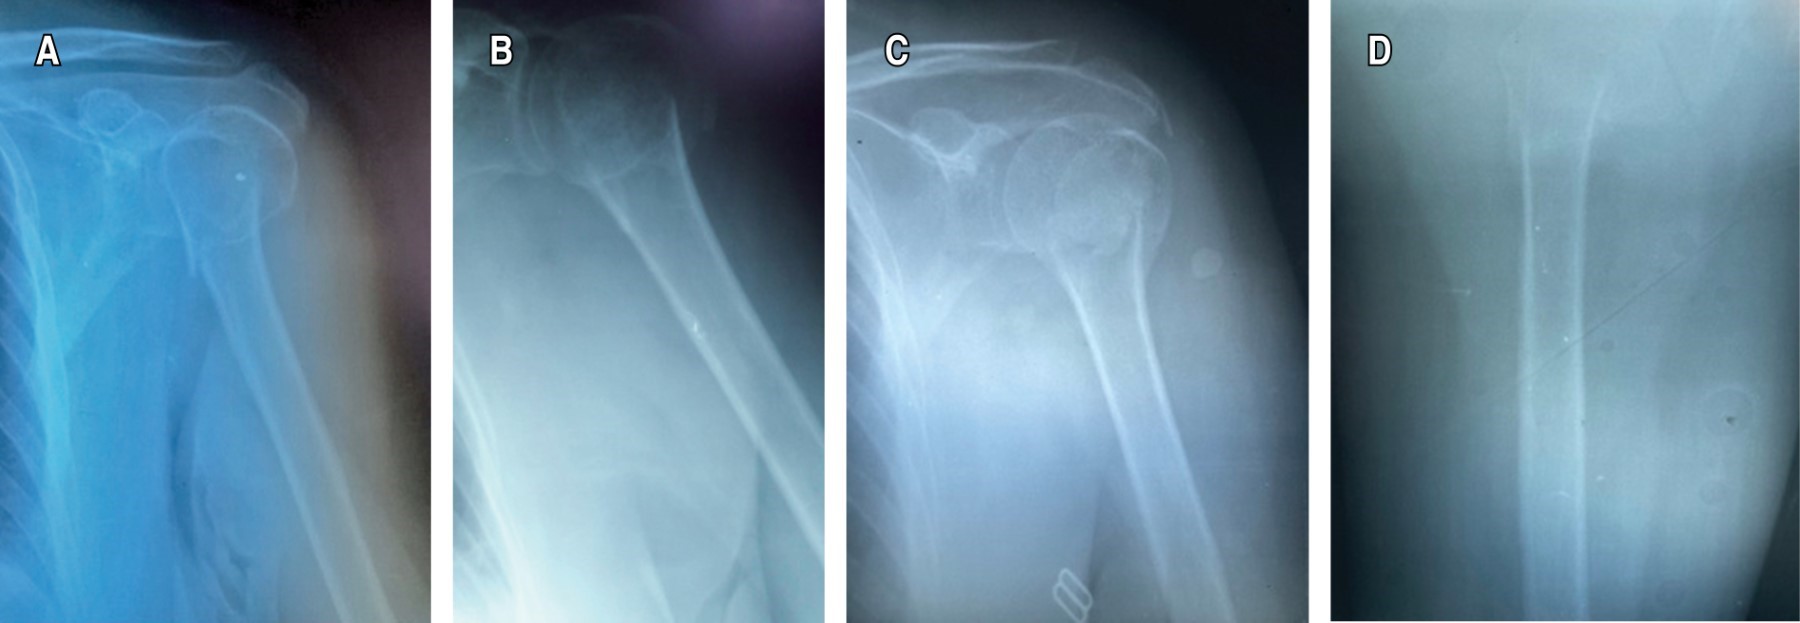

Early mobilization in the conservative management of proximal humeral fractures. A real risk?

Early mobilization is the mainstay of conservative management of proximal humerus factures. In Mexico, the immobilization time is usually 3-4 weeks, followed by rehabilitation process, for fear of the risk of complications such as non-union, despite the fact that research supports early mobilization for a better patient prognosis. Objective: To determine if early mobilization, on the seventh day of immobilization, brings radiological bone consolidation and early positive functional results in Mexican patients with Neer II proximal humerus fracture. Material and methods: This is a prospective case report of 3 patients > 50 years with a diagnosis of Neer II proximal humerus fracture, they were immobilized for seven days with subsequent early mobilization, the Constant-Murley Functional Scale, DASH Questionnaire, and Montoya radiological scale at the first, second and third month of evolution. Results: Patient 1. First month Constant Murley 26, DASH 64.1, Montoya GII, second month Constant-Murley 67.35, DASH 32.5, Montoya GIII, third month Constant-Murley 98, DASH 2.5, Montoya GIV. Patient 2. First Month Constant-Murley 44, DASH 33.3, Montoya GII, second month Constant-Murley 59.35, DASH 39.16, Montoya GIII, third month Constant-Murley 94, DASH 4, Montoya GIV. Patient 3. First month Constant-Murley 38, DASH 57.5, Montoya GII, second month Constant-Murley 67.62, DASH 10.83, Montoya GIII, third month Constant-Murley 96, DASH 5.75, Montoya GIV. Conclusion: Early mobilization in Mexican patients with Neer II proximal humerus fracture brings early excellent radiological and functional results if the patient is followed appropriately.

Figure 1

Figure 2

Figure 3

Figure 4

Figure 5

Figure 6

Figure 7

Figure 8

Figure 9

Figure 10